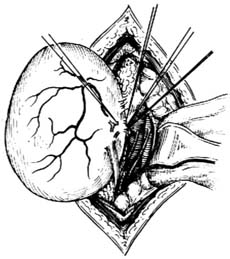

原發性腹膜後腫瘤--手術治療2.化療

(二)術前準備

1.手術範圍及危險性的判定。巨大腹膜後腫瘤(無論良性、惡性),因瘤塊巨大,血供豐富、根基寬廣及周圍器官和重要組織結構緊密粘連,要徹底切除腫瘤需聯合切除一些重要的組織或(和)器官,術中出血量常較大,術前必須了解患者的全身情況,估計能否耐受重大手術,切除某種器官是否會影響患者的生命或正常生活。

2.大量備血,一般應備2000-3000ml全血。必要時可行自體輸血。

3.擬作大血管切斷吻合或血管移植者,應準備好血管外科器械和血管移植物。

4.擬作患側腎臟切除者,術前應充分了解擬保留側腎的功能。

5.擬作結腸切除者,應作腸道準備。